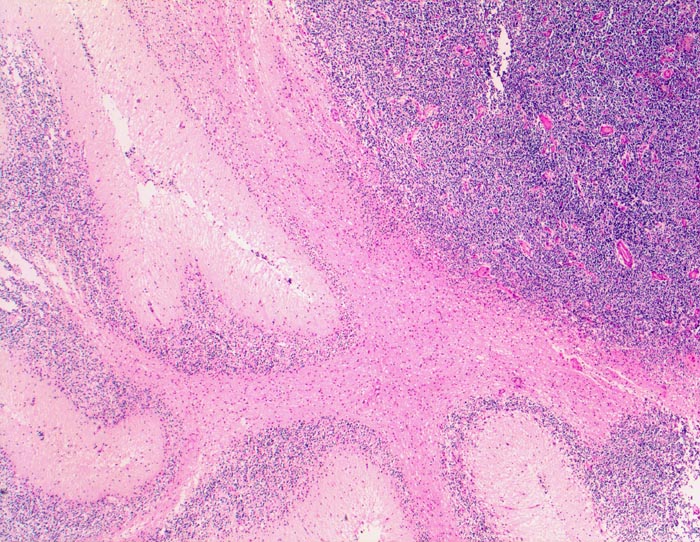

Die Makroskopie ist variabel. Meist sind Medulloblastome unscharf begrenzt, grau und weich, gelegentlich aber auch scharf begrenzt und derb.

Wegen der hohen Zelldichte und der hohen Kern-Zytoplasmarelation erscheinen die Tumoren in der HE Färbung blau. Medulloblastome müssen differentialdiagnostisch von morphologisch ähnlichen kleinzelligen undifferenzierten Karzinomen und Lymphomen abgegrenzt werden. Das klassische Medulloblastom besteht aus dicht gepackten Zellen mit runden bis ovalen oder karottenförmigen stark hyperchromatischen Kernen umgeben von wenig Zytoplasma. Runde Zellen mit weniger dichtem Chromatin sind oft beigemischt. Zahlreiche Mitosen, flächenhafte Nekrosen und Apoptosen sind typisch. In weniger als einem Drittel der Fälle findet man die typischen Homer-Wright Rosetten. Diese bestehen aus ringförmig angeordneten Tumorzellkernen um ein fibrilläres Zentrum aus Zytoplasmafortsätzen.

• Scharf begrenzter rundlicher sehr zellreicher (deshalb blauer) Tumor.